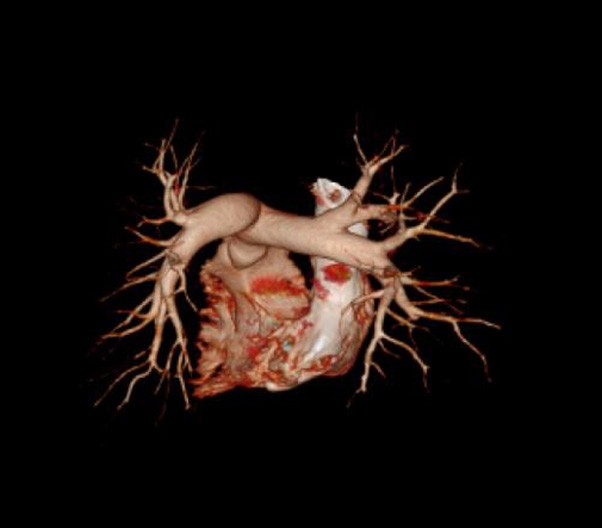

The ECG gating technology and real-time waveform analysis detect arrhythmia and abnormalities automatically, ensuring that a normal heartbeat is captured for cardiac imaging. The unparalleled multi-phase cardiac imaging makes it possible to achieve 39 ms time resolution, therefore significantly smoothens cardiac scans, even with the condition of rapid heartbeat. Furthermore, the combination of imA technology and gating acquisition provides for an 80 percent reduction in heart scan dosage radiation.